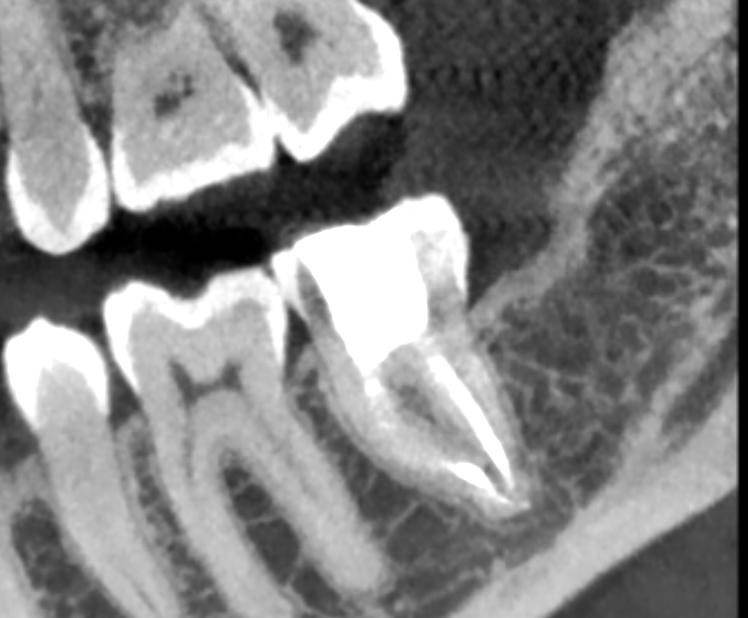

Гарриевич Опубликовано 10 часов назад Автор Поделиться Опубликовано 10 часов назад Еще один осмотр спустя 3 года и полное заживление 1 Ссылка на комментарий